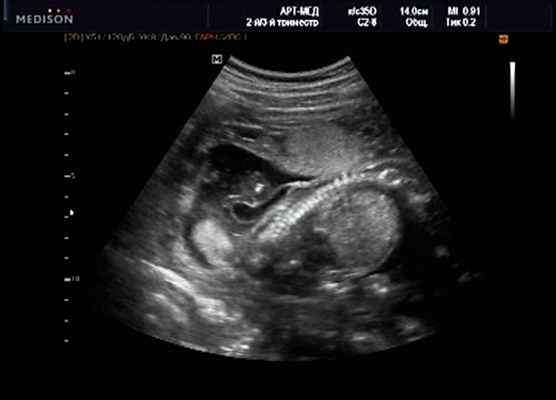

Беременная М., 21 года. Впервые обратилась в клинику в срок 20 нед беременности. Исследование проводилось на аппарате SonoAce-R7 (Samsung Medison) с использованием режима поверхностной объемной реконструкции 3D/4D. При изучении позвоночника плода в трех плоскостях костных деформаций не выявлено. В грудном отделе позвоночника обнаружено тонкостенное кистозное образование с анэхогенным содержимым, стебельчатой формы (рис. 10-12). Степень "прозрачности" содержимого была выше околоплодных вод, что позволяло идентифицировать его как ликвор. В проекции грыжевого выпячивания располагалась петля пуповины, дифференциальную диагностику которой без труда удалось провести с помощью ЦДК (рис. 13).

Рис. 10. Беременность 20 нед. Менингоцеле: типичное кистозное образование стебельчатой формы.

Рис. 11. Беременность 20 нед. Менингоцеле.

Рис. 12. Менингоцеле. В сагиттальном срезе видна неровность кожи в проекции расщелины.

Рис. 13. Петля пуповины в режиме ЦДК.